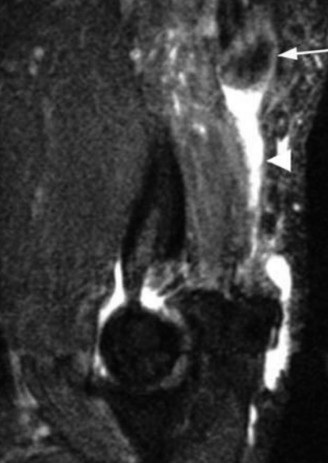

Understand common complications associated with performing surgery for scapulothoracic bursitis? CASE 33 A 42-year-old female presents to the office for follow up after sustaining a minimally displaced radial head fracture 3 months prior. She states she was initially treated in long-arm splint by the ER and did not follow up with an orthopaedic surgeon until now. Per her report, she removed the splint 4 weeks after the injury, but did not move her elbow due to pain. She now has no pain but is unable to reach that hand to her face or head. The remaining history is significant for previous ulnar nerve surgery for which she is unable to provide details. On physical examination, her upper extremity is normal except for limited flexion/extension, measured to be 80 to 50 degrees by goniometer. In addition, she has a well-healed surgical incision about the medial elbow, consistent with a previous surgery on her ulnar nerve. Her images are shown (Figs. 2–82 to 2–84).

Figure 2–82

Figure 2–83

Figure 2–84

The correct answer is (A). Classification of post-traumatic elbow stiffness allows for better understanding of the disease and allows the clinician to treat the underlying cause of the joint contracture. Intrinsic causes include: any problem within the joint such as incongruency, loose bodies, or severe osteoarthritis. Extrinsic causes include capsular tightness, muscle contracture, heterotopic ossification, and skin contractures. Early is defined as within 6 months of the injury while late is considered to be greater than 6 months after the injury. Patients that present in the early time frame have a significantly better chance at having a good result both from nonoperative and operative treatment.